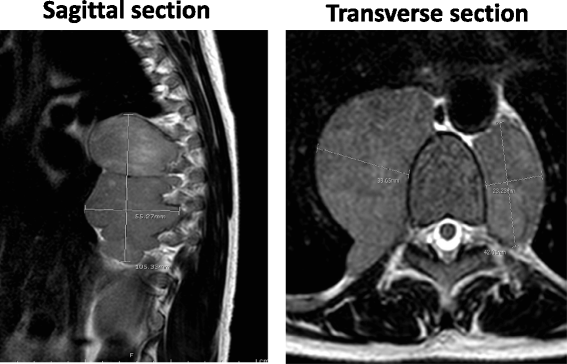

结果:血红蛋白电泳显示HbF 38%(正常0.0-2.0%,显著升高)、HbA₂ 3.8%(正常1.5-3.5%);α珠蛋白基因分析阴性(排除α地中海贫血);MRI显示T4-T11脊柱旁异质性肿块(9.7×1.6×1.0 cm),脊髓受压;CT显示肝、脾、胰腺等部位肿块,初诊考虑“转移瘤(乳腺癌或妇科来源)”。

结果:患者术后神经症状改善(双下肢麻木减轻),肌力从Ⅲ级恢复至Ⅳ级;放疗后脊柱旁肿块缩小(MRI随访未提及具体尺寸);随访期间未出现复发(文献未明确随访时间)。